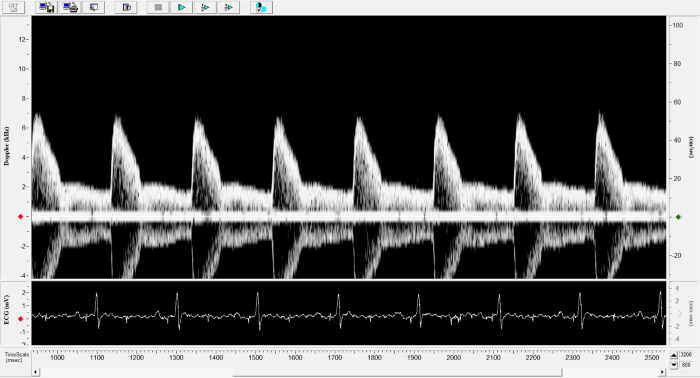

Pulmonary Flow

Pulmonary Flow. Image Credit: Scintica Instrumentation Inc.